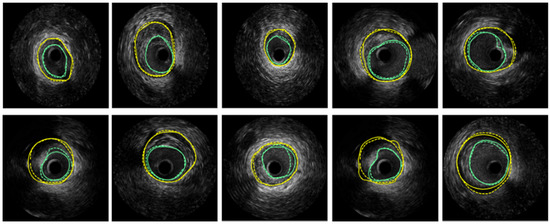

After tracking aortic cross-sections in US images, threshold technology is applied to obtain those pixels whose intensities are higher than 220 inside the aortic cross-section. The centroid of those pixels is the detected position of the cross-section of the catheter. In Figure 7, the red circle represents the tracked aortic cross-section and the green point is the located tip of catheter. Based on the positions of the catheter’s tip, the 3D trajectory of the catheter is acquired. Figure 8 shows two trajectories of the catheter, including an automatic trajectory of the catheter from our multi-feature particle filter tracking method and a 3D trajectory from the manually delineative catheter’s tip. The distance between the manual trajectory and automatic trajectory using multi-feature particle filter tracking method is 1.48 mm.

Figure 7. Tracking result of aortic cross-section and catheter’s tip in US images, (a) the US image which contains the catheter’s tip; (b) the US image which does not contain the catheter’s tip.